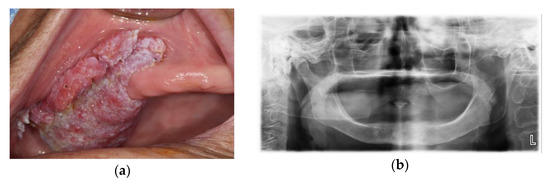

2.2. Case 2: Ameloblastoma on Left Mandibular Body and Angle

2.2.1. Computer-Assisted Surgical Planning

2.2.2. Surgical Technique